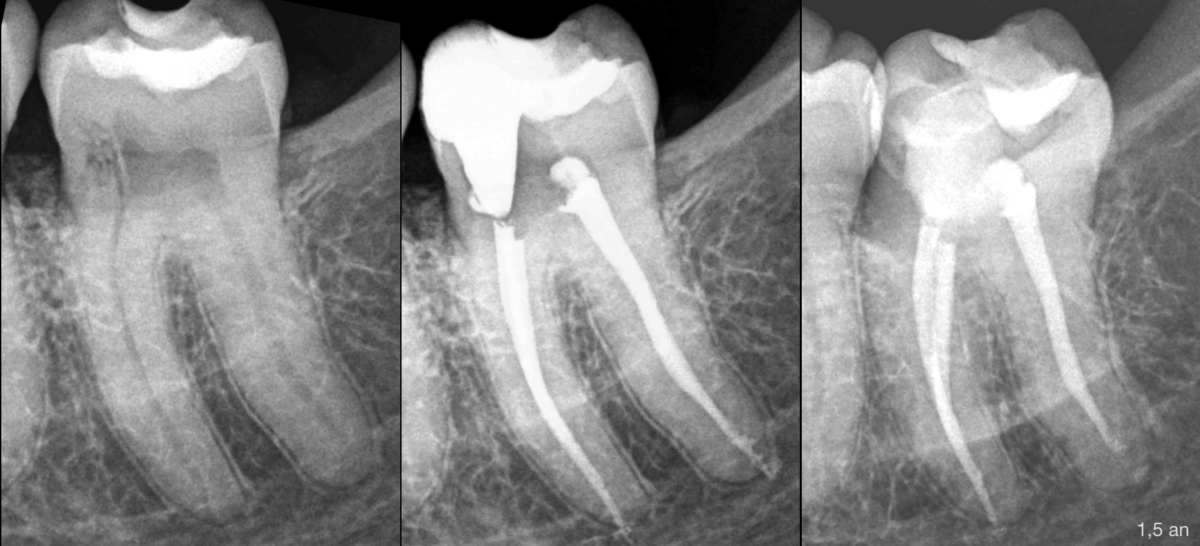

𝐐𝐮𝐞𝐥 𝐜𝐡𝐚𝐧𝐠𝐞𝐦𝐞𝐧𝐭 𝐩𝐨𝐮𝐯𝐨𝐧𝐬-𝐧𝐨𝐮𝐬 𝐨𝐛𝐬𝐞𝐫𝐯𝐞𝐫 𝟏 𝐚𝐧 ½ 𝐚𝐩𝐫𝐞̀𝐬 ?

–> Un wash out (élimination/disparition) de biomatériau dans la partie apicale

⚠️ Il s’agissait très probablement d’une sortie apicale vestibulaire ou linguale, quelques mm au-dessus de l’apex radiographique.

Le puff de biocéramique s’est fait éliminer avec les remaniements osseux.